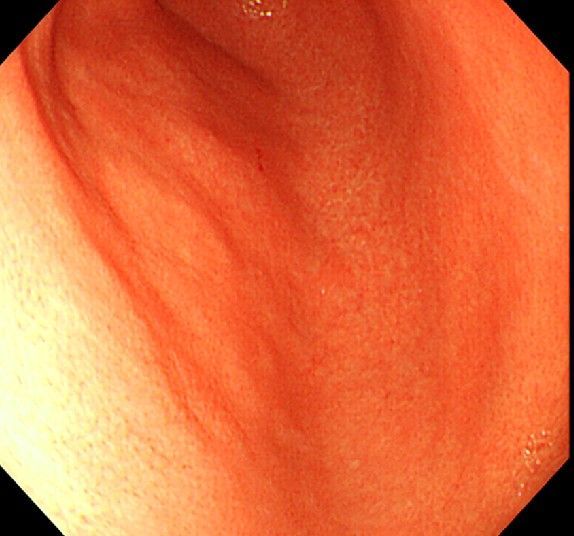

위 내시경을 찍었는데 위염 종류 사진을 알 수 있을까요? (사진 많습니다..)

한달 전 쯤에 소화불량과 속쓰림이 3개월 동안 약을 먹어도 낫지 않아 위 내시경을 찍었는데 위에 염증이 많이 있다는 이야기를 들었습니다...그런데 상태가 얼마나 안 좋은지 어떤 종류의 위염인지에 대해서는 물어봐도 안 알려주셔서 여기에라도 올려서 여쭈어봅니다... 제 상태가 얼마나 심각한 걸까요..

사진상으로 보아서는 정상에 가까운 점막상태이거나 약간의 표재성 위염이 있는 정도로 보입니다.

홍반성 위염이 있으며 경증의 역류성 식도염이 있습니다

위내시경상으로는 특이소견이 없다고 보셔도 됩니다